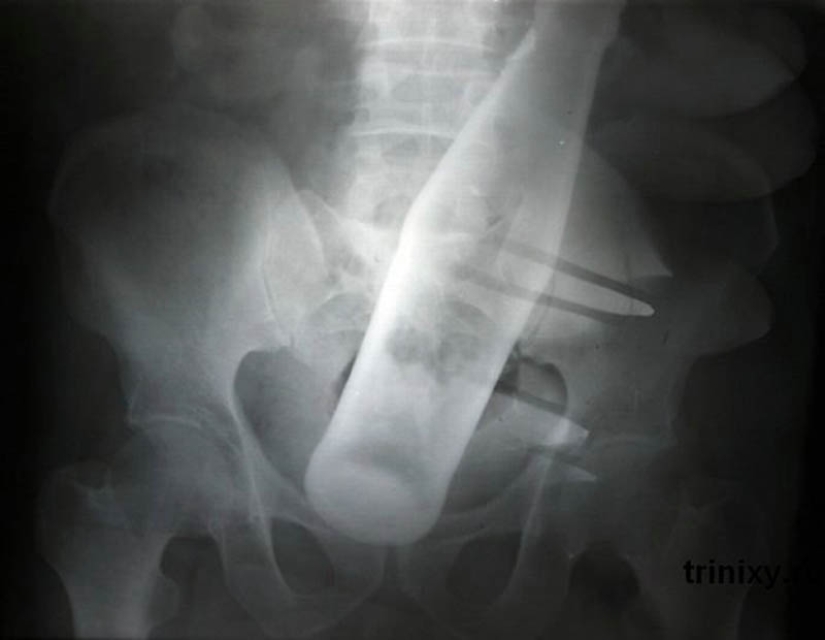

20. Una botella de Pepsi en el ano de un hombre de 60 años.